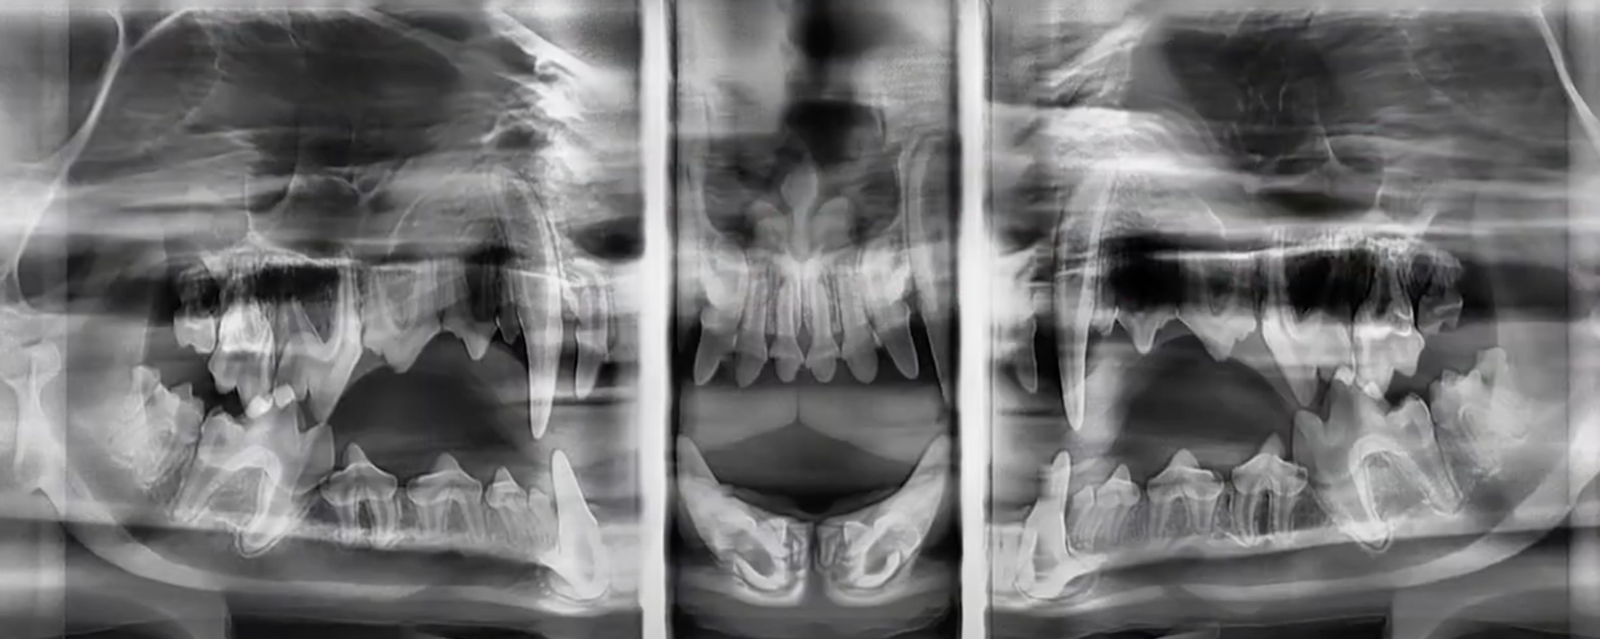

We are proud to offer advanced dental services, including state-of-the-art veterinary panoramic dental radiography. Dental radiographs are essential for assessing the health of every tooth and its surrounding structures, allowing us to detect periodontal disease that may not be visible during a standard oral exam.

Periodontal disease is common in pets and, when moderate to severe, can lead to oral discomfort and bone loss at the tooth root. During dental cleanings or advanced oral procedures, we combine thorough oral exams, periodontal probing, and dental radiographs to determine which teeth require deep cleaning and which may need extraction.